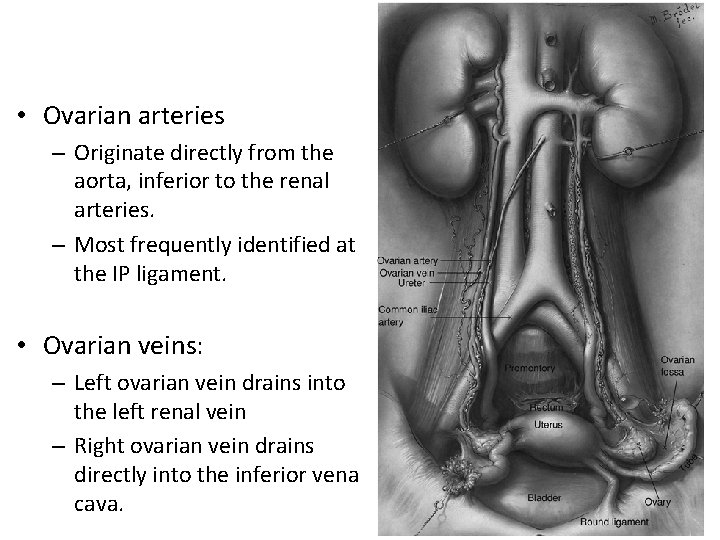

• Ovarian arteries – Originate directly from the aorta, inferior to the renal arteries. – Most frequently identified at the IP ligament. • Ovarian veins: – Left ovarian vein drains into the left renal vein – Right ovarian vein drains directly into the inferior vena cava.